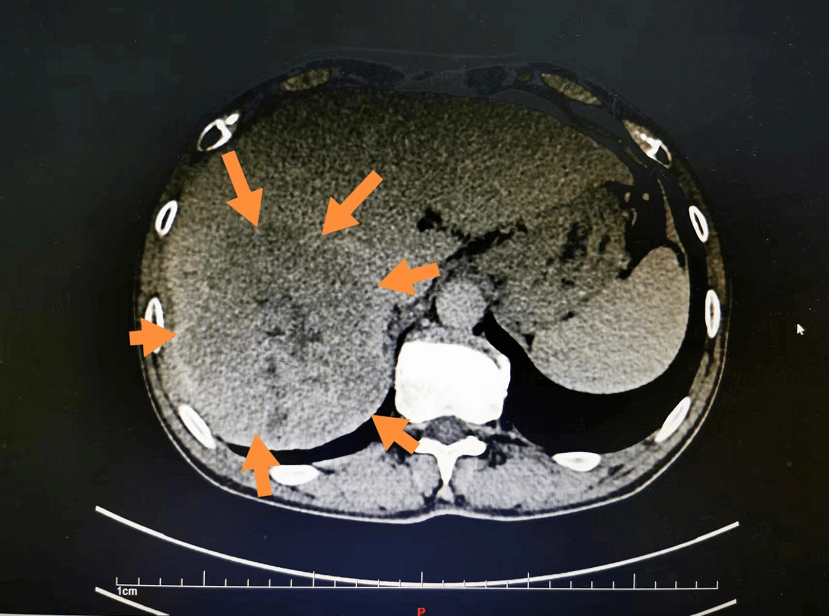

临床工作黔南州人民医院肝胆外科实施精准肝切除治疗危险部位肝脏肿瘤

图片尺寸1080x530